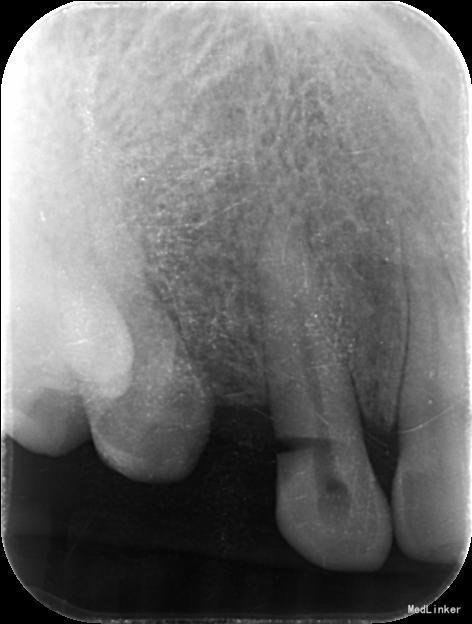

检查: 13唇侧颈部深大楔形缺损,探及髓腔,无探痛,叩痛不适,无松动,牙龈未见明显异常,牙髓电活力测试无反应。 X线示:13冠部低密度影像至髓,根尖区见低密度影像。

诊断:13慢性根尖周炎 治疗计划:13根管治疗后冠修复 治疗:1. 13去腐,腭侧开髓暴露髓腔,降牙合,探查根管,干燥根管,电测工作长度WL=25mm,此时根尖区探痛明显,按此长度插针拍片示超出根尖孔4mm,推算出WL=21mm。EDTA下,常规预备至35#,3%过氧化氢和生理盐水冲洗+超声荡洗根管交替进行。隔湿,干燥根管,封CP棉球, 氧化锌水门汀暂封。嘱勿用患牙咬物。 2.主诉:右上前牙上次治疗后后无不适。 检查:13暂封物在,叩痛(-),牙体无松动,牙龈未见明显异常。 处置:13去除暂封物,生理盐水冲洗并干燥根管,试尖到位,进口根充糊剂+牙胶尖冷侧压根管充填,氧化锌水门汀暂封,术后拍片示:13根充恰填。嘱勿用患牙咬物。 建议:13冠修复